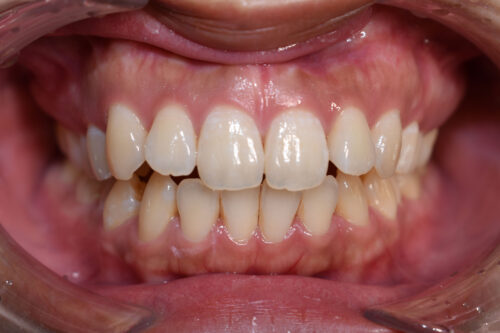

ワイヤー矯正治療11か月後です。

ワイヤー期間 11か月, 17回来院

本症例のように

屋根のように 上下の歯が 唇側に傾斜しており

口元が出っ歯に見えるのを気になさる患者様も多くいらっしゃいます。

昔は 第一小臼歯を4本抜歯して 矯正治療をしましたが、

今は 歯科矯正用アンカースクリュー(デュアル・トップオートスクリュー)を利用する

ことで

歯を抜かなくても 歯列全体を後方へ移動することができるようになりました。